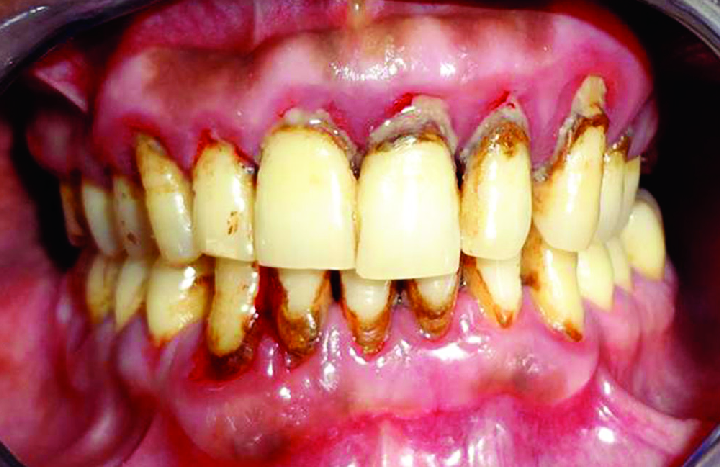

사진이 좀.. 부담스러우실 수 있으니 각오를 하고 보셔야 합니다...! (전 사실 별 감흥이 없습니다만..)

이러한 엄청난 치석을 만났을 때, 가장 먼저 해야하는 것은 '치석제거 = 스케일링' 입니다.

정확히는 눈에 보이는 잇몸 '상방'의 치석을 제거하는 술식입니다.

이런 사진 정말 죄송하지만 (그래서 일전에 경고를..! ㅠㅠ) 정말 치석이 어디까지 있을지 예측도 안되는 분들도 있습니다.

전체적으로 이럴수도 있고, 어금니만 이럴수도 있고....

그런 분들은 수술적 잇몸치료를 시행하여야만, 구석구석 꼼꼼히 잇몸치료를 해드릴 수 있어요.